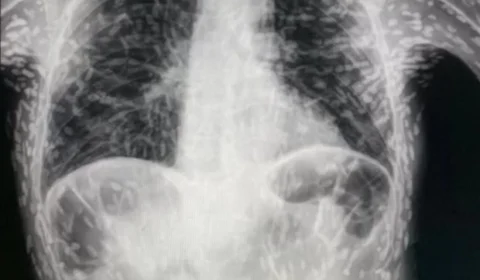

Tecnologia de empresa em SP faz diagnóstico de mesmo parasita revelado em tórax de paciente; conheça

Médico paulista compartilha em rede social exame de paciente com ovos de tênia no tórax e explica o diagnóstico de cisticercose.